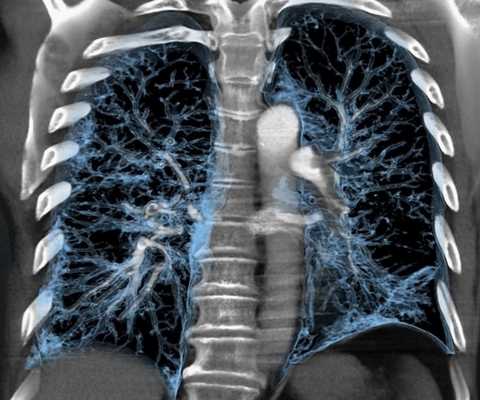

Мультиспиральная КТ грудной клетки, 3D-реконструкция

В результате получают фотографии аксиальных срезов, с помощью которых достраивают сагиттальную и фронтальную проекции. Для уточнения локализации патологического очага и оценки взаимного расположения анатомических структур средостения реконструируют 3D-модель рассматриваемой зоны.